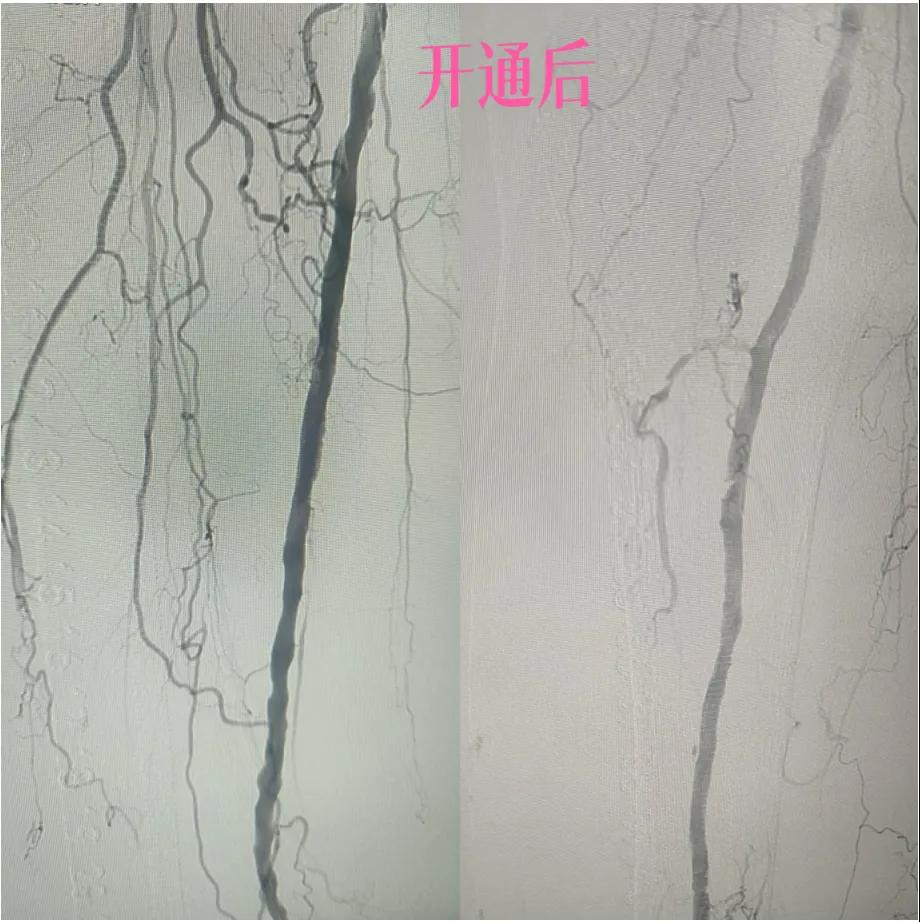

為了挽救患者的患肢,避免截肢,外二科血管外科介入團(tuán)隊(duì)經(jīng)過(guò)縝密的術(shù)前討論和評(píng)估,決定采用目前微創(chuàng)介入技術(shù)——下肢動(dòng)脈藥涂球囊擴(kuò)張成形術(shù)(DCB)。

2.  “探路”與“疏通”:在先進(jìn)的DSA(數(shù)字減影血管造影)設(shè)備實(shí)時(shí)引導(dǎo)下,猶如擁有了“透視眼”,導(dǎo)管導(dǎo)絲巧妙穿越病變血管的狹窄、閉塞段。這需要極高的技巧和對(duì)血管解剖的深刻理解。

3.  “球囊發(fā)力”:到達(dá)目標(biāo)閉塞段后,將未充氣的球囊導(dǎo)管送至病變部位。隨后,精準(zhǔn)控制壓力,使球囊緩慢充盈擴(kuò)張,如同在血管內(nèi)部進(jìn)行精細(xì)的“拓荒”,將堵塞的斑塊擠壓、塑形,撐開狹窄的血管腔。

4.  即刻“見(jiàn)證”:再次造影顯示,原本狹窄閉塞的血管段血流恢復(fù)通暢!足部遠(yuǎn)端血管顯影較前明顯改善。手術(shù)過(guò)程順利,患者靜息痛較前明顯改善。